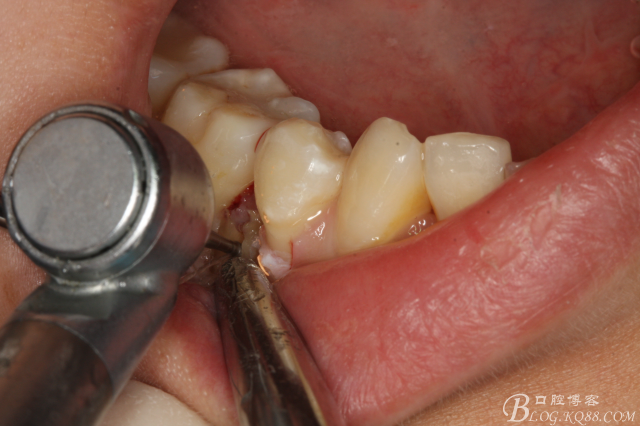

圖8.高速球鉆去骨約3mm.

圖9.暴露45頰側(cè)根面約1/2.牙根與44、46牙根緊緊相鄰。無法直接用挺。